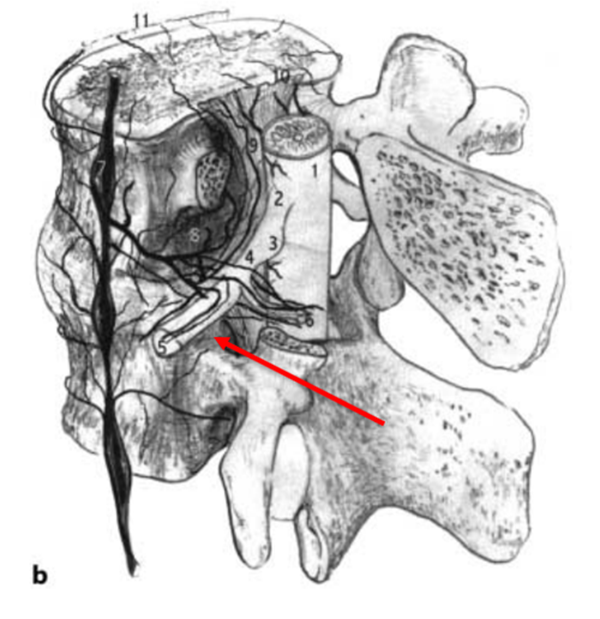

无论是RN入路还是SP入路,两种注射方法均是把药物注射至神经根的背侧或侧方,而通过对神经解剖学的认知,人们认识到,为了缓解神经疼痛,需要把药物注射至腹侧硬膜外间隙,即椎间盘/硬膜交界处、椎弓根的内侧,使得药物覆盖神经根,才能更为有效。所以,最理想的方案应该是把穿刺针通过穿刺置于椎间盘的背侧,硬膜囊的腹侧。通过解剖学发现,尽管脊柱通过骨性结构及韧带结构把重要的脊髓神经保护其中,形成一个相对封闭的结构,但仍保留了与椎管相同的孔道,正像圣经中所言:“when God closes this door, he will open another door for you”,而这扇窗,就是椎间孔。

其实早在1973年,Parviz kambin教授就提出了kambin三角,kambin三角较Bogduk三角拥有更大的空间结构,能有效避开重要的神经和血管。因此,利用Kambin三角进行穿刺,将穿刺针尖置于病变间隙硬膜囊腹侧,同时具备了安全和有效的特点。Jasper JF于2007年介绍了这种方法,他将这种方法称之为Retro-discal approach(RD)入路。Jasper认为,一个最佳的注射位置应该是使得药物覆盖椎间盘病变区、椎间盘神经界面和受刺激的节段性神经。这种穿刺方法同时也是经皮椎间孔镜置入工作通道的路径,更为外科医生所熟悉,也使得“经椎间孔注射术”名副其实。该方法成为了脊柱外科医生、疼痛科医生和神经外科医生最为推崇和认可的穿刺方式。在2014年,NASS把经椎间孔注射术写入了《腰椎间盘突出症诊疗指南》中,推荐等级为A级。